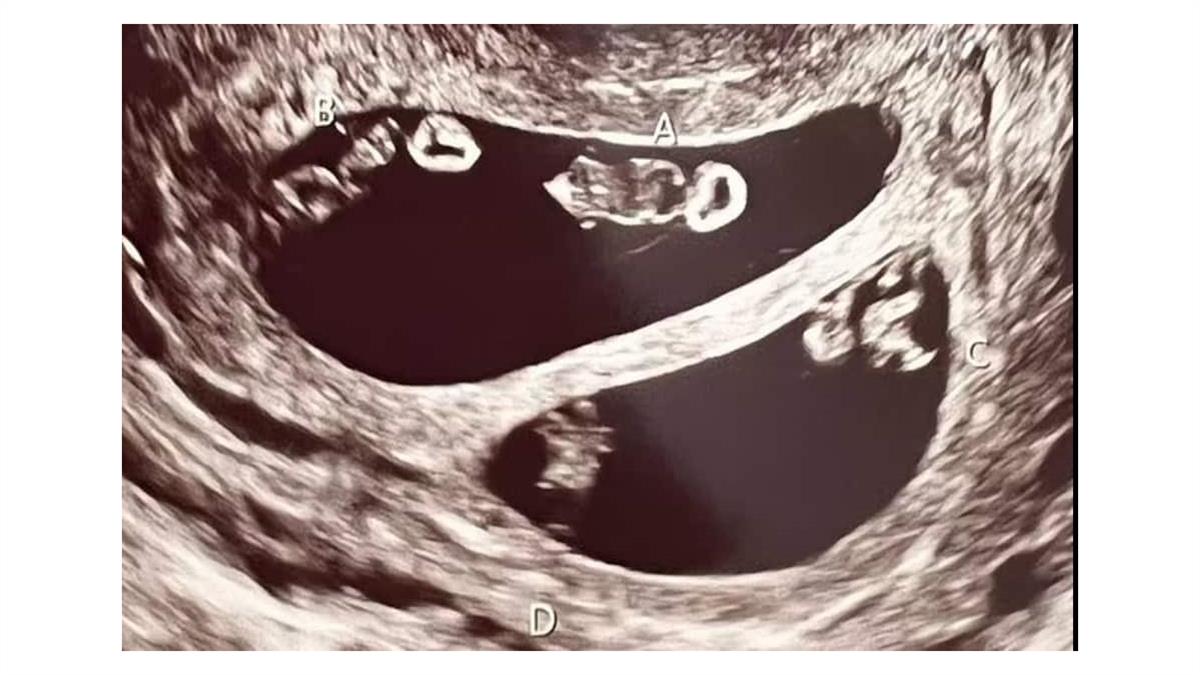

La estilista estadounidense Ashley Ness pasó de la alegría a la conmoción luego de que sus médicos le informaran de su inusual embarazo. Y es que el proceso de concepción que la mujer se realizó resultó en dos juegos separados de gemelos: dos niños y dos niñas.

Tras años de lucha contra la infertilidad y abortos espontáneos, Ness, de 35 años, optó por experimentar una concepción en la que dos de sus óvulos fueron fertilizados al mismo tiempo, antes de que ambos se dividieran.

La mujer explicó al Daily Mail que la técnica de ultrasonido no creía lo que estaba viendo, por lo que tuvo que salir de la sala de ecografía para consultar en internet si el hecho era factible.